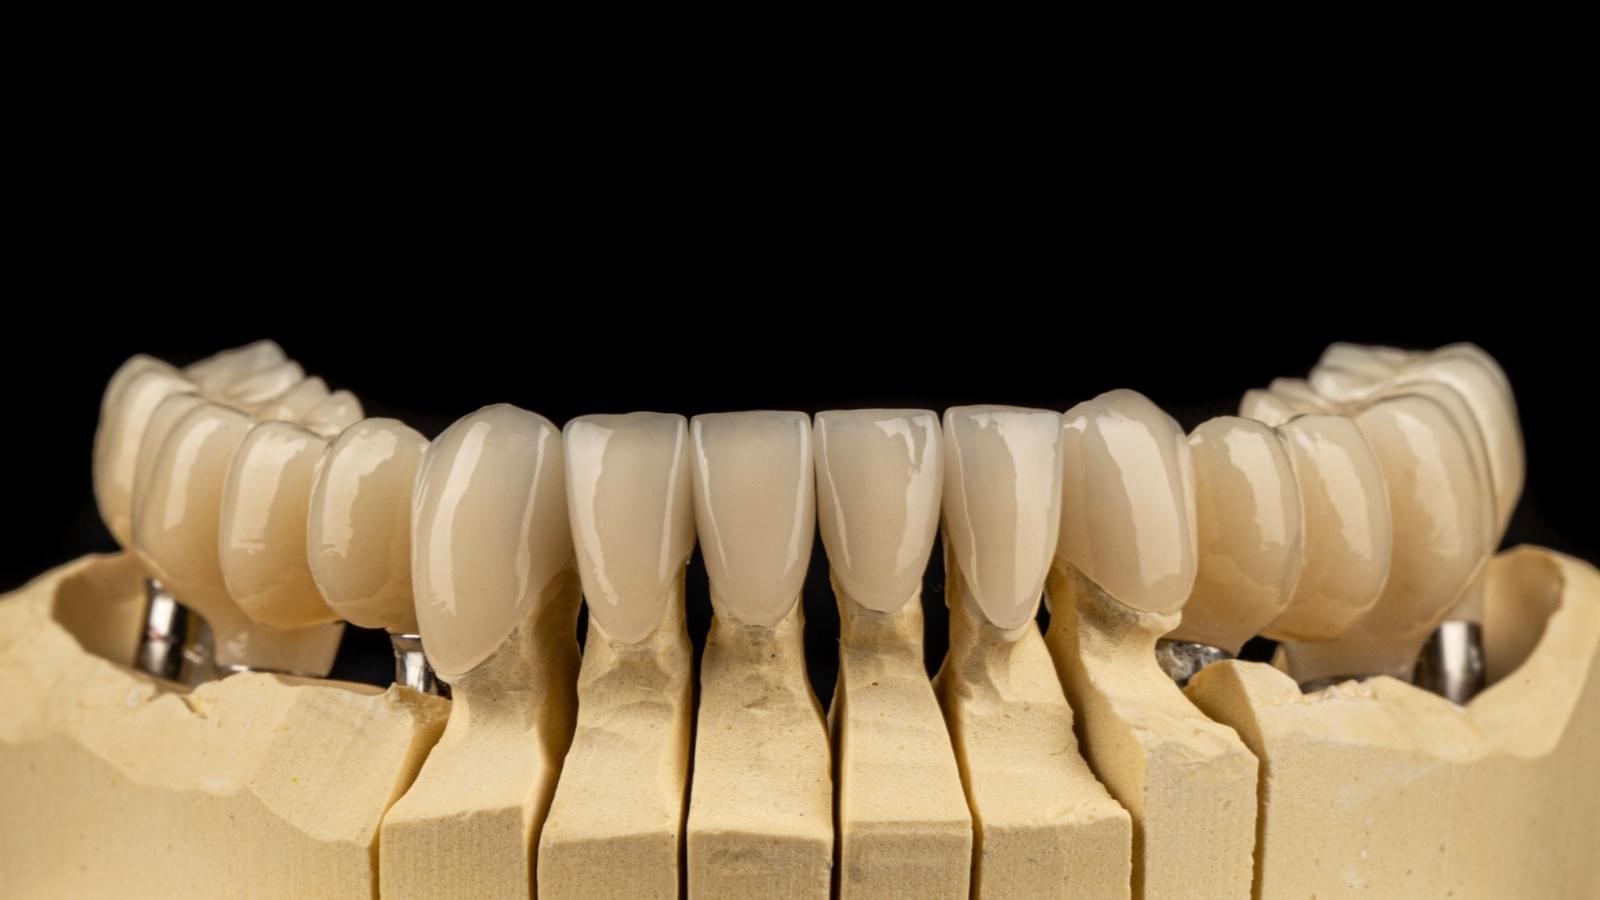

Implanturi Dentare 🔥 Cazuri finisate #1